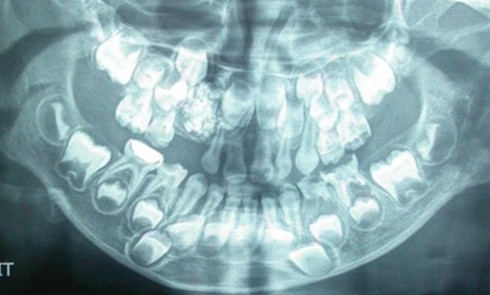

Article réservé à nos abonnés À propos d’une image radio-opaque du maxillaire

1. Quel diagnostic évoquez-vous ? a. Un ostéome b. Un améloblastome c. Un odontome complexe d. Un odontome composé e. Aucune...